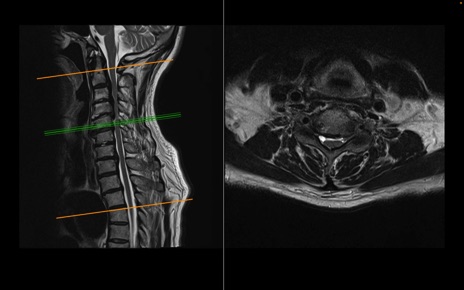

頚椎MRI

T2WI(横断像)

T2WI(矢状断像)